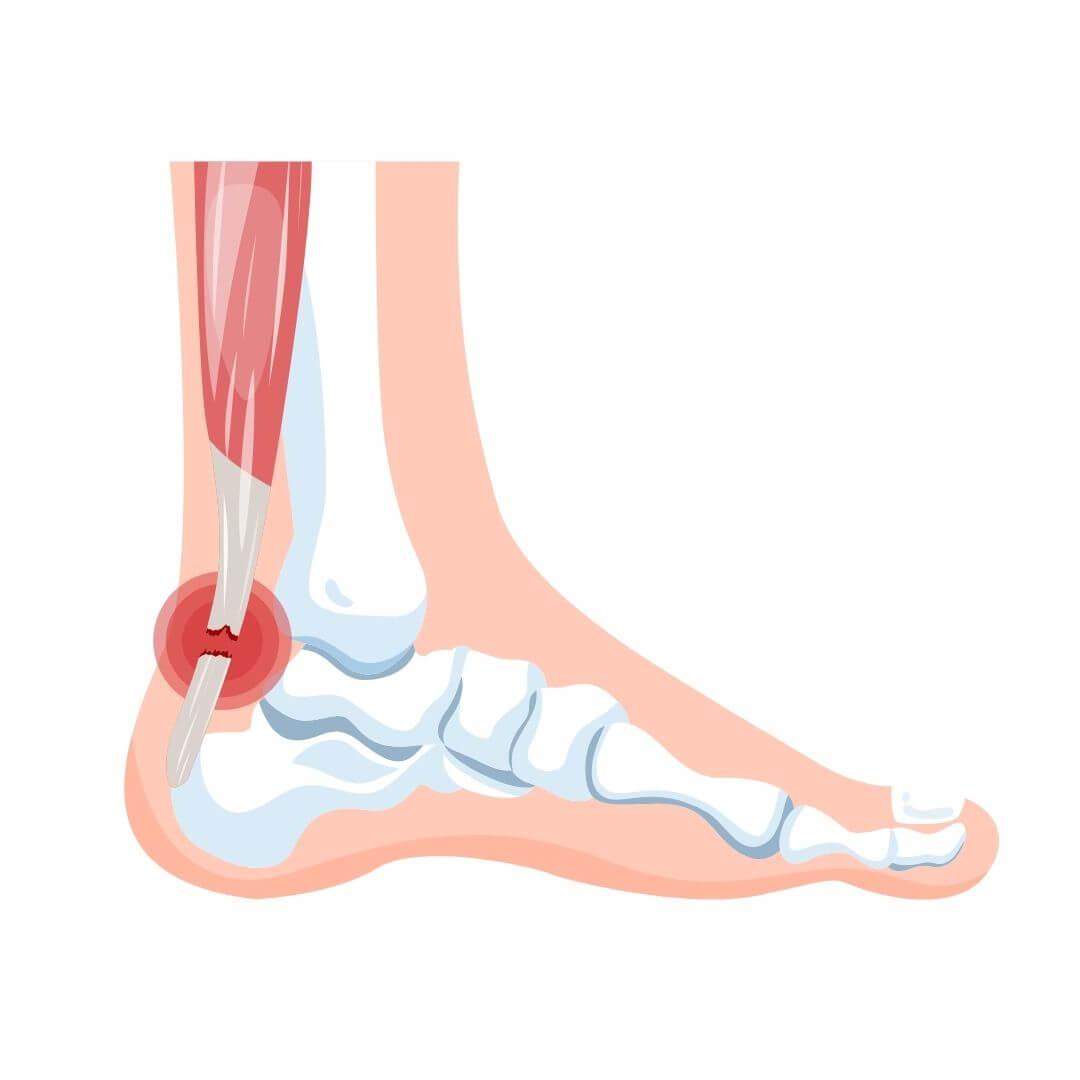

Peesscheur illustratie

Peesscheuren komen het meest voor in de:

• Schouder (rotator cuff ruptuur)

• Achillespees (achillespeesruptuur)

• Bicepspees (bicepspeesruptuur)

• Knie (quadriceps- of patellapeesruptuur)